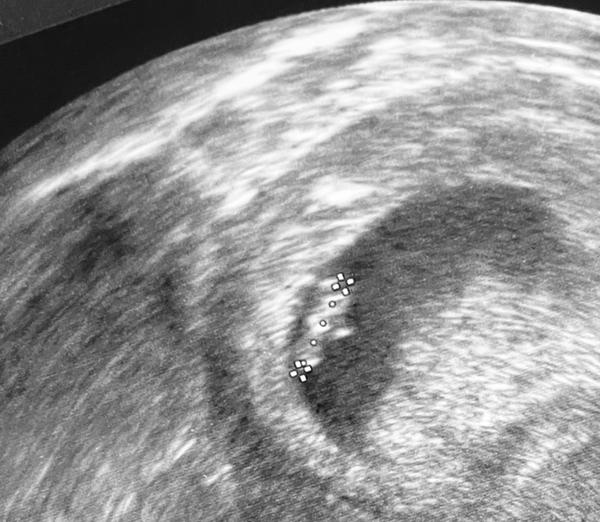

Holky vyzna se v tom někdo ? Já tedy ne 😁 poslední Ms jsem měla 19.srpna , cykly jsem měla delší cca 35 ,31 dní ovulace byla kolem toho 19 dne .. první pozitivní test jsem měla 18.zari večer .. na první kontrole jsem byla teď v úterý . Těhotenství potvrzeno , srdíčko ještě nebylo vidět ..podle ultrazvuku jsem byla v úterý 6+0. Plus minus deset dní jestli jsem to správně pochopila 😃 mám se stresovat nebo je to vpohode.. Doktror se mě ptal ,jak mám dlouhé cykly a říkal ,že to tedy odpovídá .jen mě trošku znervózňuje to srdíčko. Na další ultrazvuk jdu 25.10

@callipsa Srdíčko může být vidět klidně až 8tt... Buď v klidu.